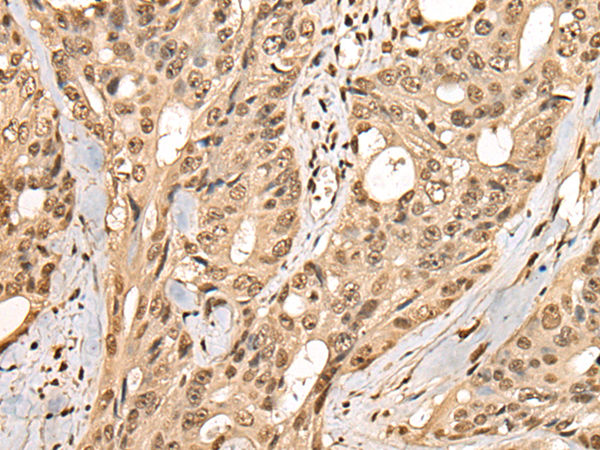

- The image is immunohistochemistry of paraffin-embedded Human colorectal cancer tissue using P02393(PHF21A Antibody) at dilution 1/50. (Original magnification: ×200)